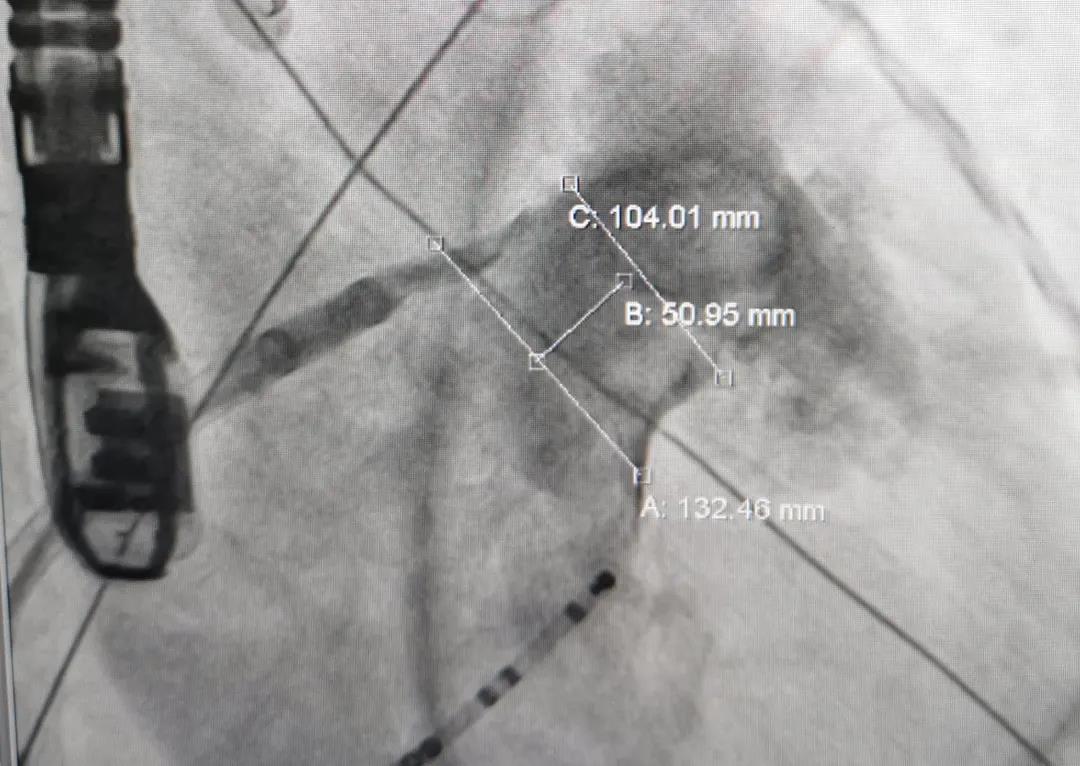

患者男,63岁,间断心悸病史11年。术前TEE显示左心耳无血栓,拟行房颤射频消融联合左心耳封堵术。左心耳测量锚定区约为27mm,封堵区约为25mm,选用LAmbre™2632封堵器进行封堵,达到了理想的封堵效果。LAmbre™独特的锚定机制能确保左心耳封堵器稳定牢固,牵拉测试十分稳定,符合COST原则,随后释放封堵器。

患者女性,71岁,因心慌气促20余天入院治疗,患有高血压及糖尿病史。多角度测量显示左心耳开口锚定区约为21mm,封堵区约为26mm,综合评估后选用LAmbre™2436封堵器,造影及食道超声显示无残余分流,患者术中、术后无不适,手术圆满成功。